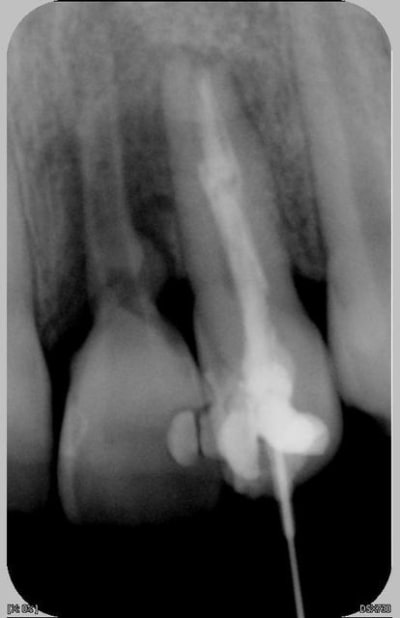

Patiente de 11 ans ayant la 21 expulsée début avril 2006. La dent a été repositionnée en centre de soins. Dans un premier temps, pas de perte de sensibilité. Puis dans un deuxième temps, comme un goût de ça tourne mal avec certainement rhyzalyse interne de la 22 (traitement thermafil pas d'école).

la on est dans un tres beau cas de resorption inflammatoire des 21 et 22

pour la 21,ne pas toucher au fantome de racine qui reste,il va disparaitre

la 22 :evident,reprise du traitement endo

Ci joint la première radio de ces dents avec attelles centre de soins universitaire